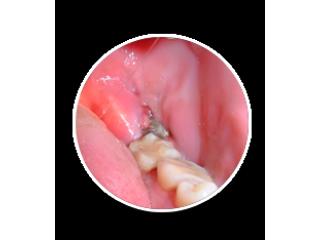

How Wisdom Teeth Infection Removal Helps Pain Fast

Wisdom Teeth Infection Removal provides fast and effective relief from pain, swelling, and dental infections. Get safe treatment from experienced dentists using advanced methods. Our affordable and premium care ensures quick healing and comfort. Choose Wisdom Teeth Infection Removal for reliable, same day dental services and restore your oral health with expert support when you need it most.